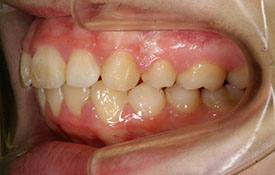

インビザラインの治療例:CASE-2

| プロフィール | 15歳 男性 |

|---|---|

| 所見 | アメリカから転院されて来られた方です。 インビザラインで上下顎の矯正治療を開始し下顎はアメリカで終了しており、上顎のみ治療の後期を担当しました。 アイライナーの装着は、1日平均22時間ほどでした。 |